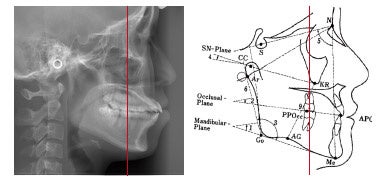

まず患者さんの骨格から診ていくというアプローチで臨みます。

それは背骨に乗っている頭の位置、頸椎の位置を正しい位置にし、そこに乗る頭蓋の位置を頸椎に対して正しくします。

右:歯並びをよくするには顎関節を正しい位置に戻すことが大事なポイント

つまり顎の関節の長さや形を整え、噛み合わせのバランスを良くすることから診ていきます。

これで治せば歯は自然と美しく整列していきます。この理論により、